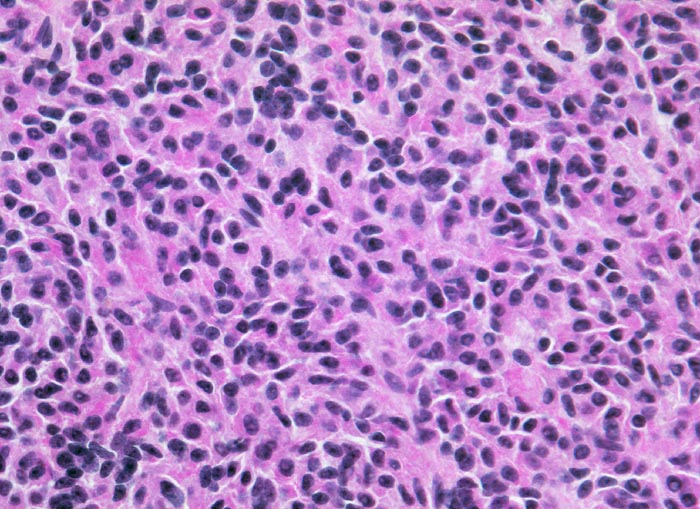

diffus wachsendes chromophobes Hypophysenadenom

Tumorzellen mit kleinen spindeligen Kernen und reichlich eosinophilem Zytoplasma.

Expression von Prolactin in 100% der Tumorzellen (Prolactinom), herdförmiger Expression von ACTH in isolierten Zellen und in vereinzelten Tumorzellverbänden. Expression von Beta-TSH in isolierten Tumorzellen. MIB-1-Index weit unter 1%. Vereinzelte epithelialisierte Zysten, sehr wahrscheinlich der Pars intermedia entsprechend.

Hypophysenmakroadenom mit erhöhtem Prolaktinspiegel